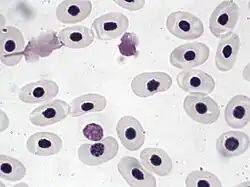

In non-mammals

Human blood is typical of that of mammals, although the precise details concerning cell numbers, size, protein structure, and so on, vary somewhat between species. In non-mammalian vertebrates, however, there are some key differences:[19]

- Red blood cells of non-mammalian vertebrates are flattened and ovoid in form, and retain their cell nuclei.

- There is considerable variation in the types and proportions of white blood cells; for example, acidophils are generally more common than in humans.

- Platelets are unique to mammals; in other vertebrates, small nucleated, spindle cells called thrombocytes are responsible for blood clotting instead.